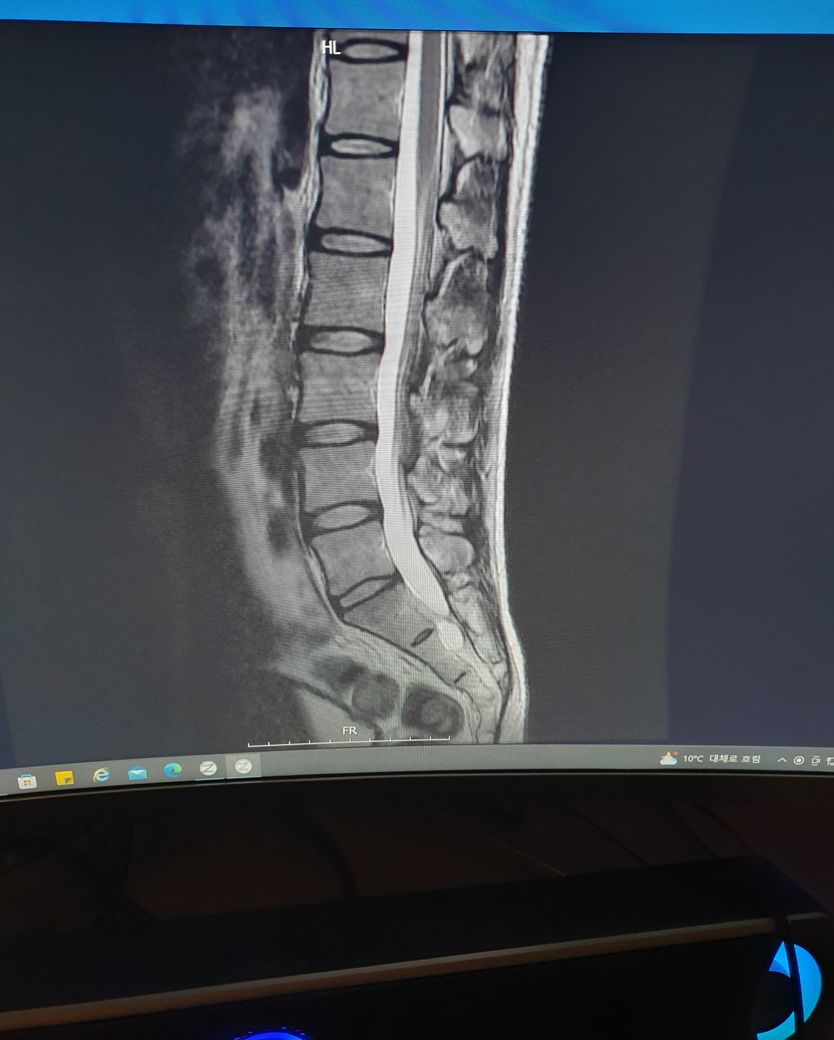

허리mri사진좀 봐주세요 ㅠㅠ만성통증

엉덩이 위쪽에전반적으로 뻐근한통증이 있습니다..ㅠ

하지 저림증상은 없구요...5번1번이 굉장히 좁은거 같은데..많이 안좋나요??

MRI로 보면 너무너무 건강한 허리입니다.

요추 5번 천추 1번 사이는 다른 요추들 사이의 디스크보다 당연히 좁아보일 수 있습니다.

지금 증상은 디스크 내장증 증상일 가능성이 있으며 요추 전만 자세만 잘 취해주시면 금방 좋아지실겁니다.